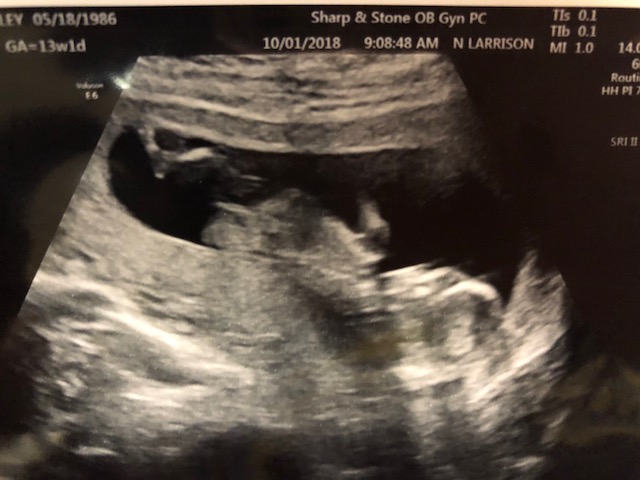

I went and got another ultrasound I don't think the baby was cooperating lol. Here are two of the best pics which i think may have a nub. What do you ladies think? I would love any guesses.Attachment 40481Attachment 40482

Not the best shots due to arching back (awwww!!) but tentative pink lean!